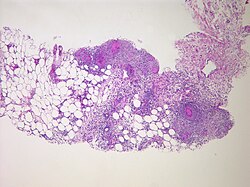

Peritonit — (lat. peritoneum periton yaxud qarın boşluğunu örtən seroz qişa + lat. -itis iltihabi göstərən şəkilçi) peritonun iltihabı, qarın boşluğunun iltihabı.